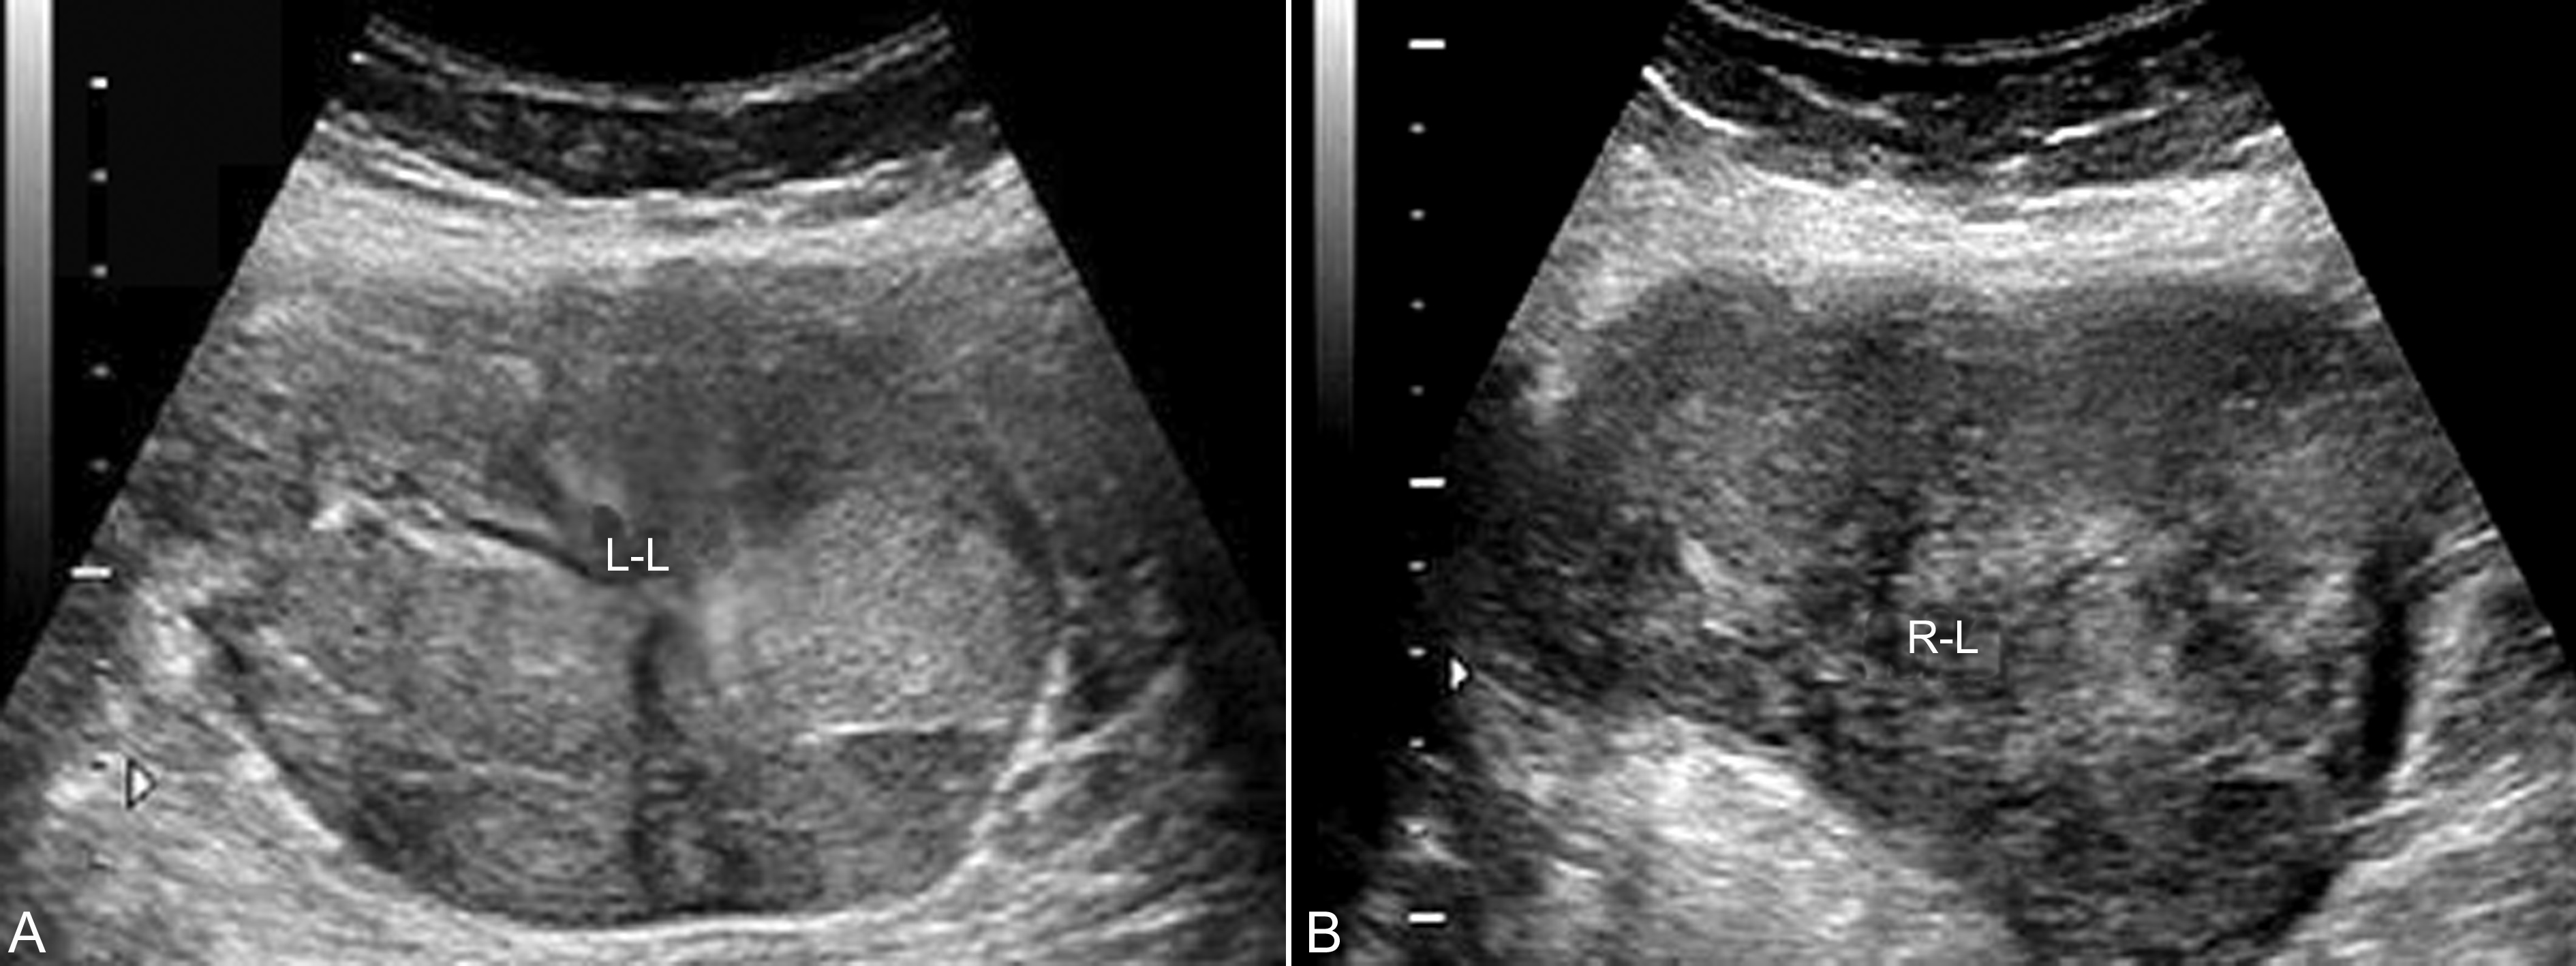

3.黄体瘤 妊娠黄体瘤(luteomas of pregnancy)又称妊娠黄素瘤,是妊娠期少见卵巢瘤样病变,多发生在妊娠3个月后,至2014年,文献报告的病例不超过200例。黄素瘤的发生可能与此时期的雄性激素水平升高有关,瘤体大小变化很大,大者直径可以达到20cm,平均直径6cm~8cm。在妊娠中后期孕妇可以出现嗓音低沉、面部*疮痤**、多毛、阴蒂肥大等雄激素作用,并可影响胎儿。超声检查显示为妊娠子宫一侧或双侧的实质性回声,形态多显示规则,内部显示为均匀或不均匀的的实质性回声(图2),内部有时可显示分隔征象;当黄体瘤内部有出血时可显示不均匀的回声;CDFI检查有时可以显示血管进入瘤体内(图3),有时可显示内部丰富的血流信号。由于超声显像检查可以发现合并腹水,孕妇血液检查有AFP和CA25升高,但同时合并的血液雄激素的升高以及孕妇男性化的表现可以提示卵巢黄素瘤。分娩后黄素瘤即开始缩小,随着体内激素水平的逐渐恢复,多数在分娩后三个月左右完全消失。

图2双侧黄体瘤声像图 显示为不均匀实性回声。L-L:左侧卵巢黄体瘤 R-L:右侧卵巢黄体瘤